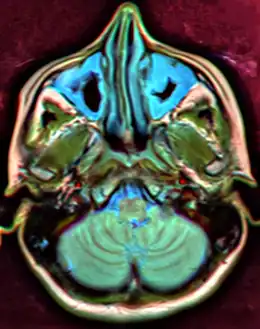

Other namesSinus infection, rhinosinusitis

A CT scan showing sinusitis of the ethmoid sinus